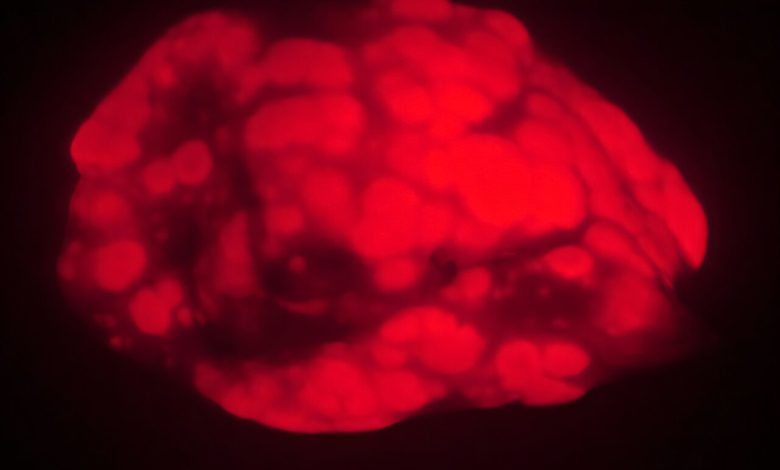

Camundongos velhos desenvolvem menos tumores pulmonares e menores (vermelho) do que animais mais jovens em um modelo de câncer. As descobertas sugerem que, em animais ou humanos muito idosos, o processo de envelhecimento suprime a formação de cancro. Crédito: Emily Shuldiner

Ratos de laboratório antigos desenvolvem substancialmente menos tumores pulmonares e menos agressivos do que animais mais jovens, num novo estudo liderado por investigadores da Universidade de Stanford. A descoberta vai contra o dogma estabelecido que afirma que o risco de cancro aumenta com a idade, mas enquadra-se com o que é observado em pessoas muito idosas, nas quais o risco de cancro parece estabilizar ou mesmo diminuir com a idade.

Uma vez que os animais tinham dentes suficientemente longos, Shuldiner induziu a formação de câncer de pulmão. Quinze semanas depois, a quantidade de cancro nos pulmões dos ratos jovens – medida pelo peso pulmonar e imagens fluorescentes – era cerca de três vezes maior que a dos ratos mais velhos. Os ratos jovens também tinham cerca de três vezes mais tumores, e estes tumores eram significativamente maiores do que os encontrados em animais velhos.